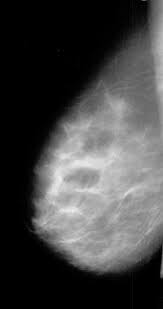

Découvrez les similitudes et les différences entre la mammographie 2d et 3d. Les mammographies constituent un outil précieux pour la détection précoce du cancer du sein, bien que de nombreuses femmes soient préoccupées par la douleur qu'elles peuvent causer.

La mammographie permet grâce à de faibles doses de rayons x l'obtention de clichés permettant de détecter certaines anomalies de la glande mammaire. La mammographie est indiquée à partir de l'âge de 50 ans, tous les deux ans, jusqu'à l'âge de 74 ans. Pourtant, le cancer du sein peut être guéri dans plus de 9 cas sur 10 lorsqu'il est détecté tôt.

La mammographie est une des principales méthodes de détection de la maladie. Il est également utilisé à des fins de diagnostic. Une mammographie en 3d regarde une mammographie numérique 2d standard prend deux vues du sein, comprimant de haut en bas et de côté à côté.